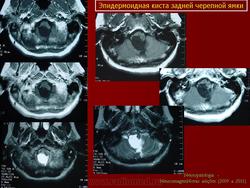

Эпидермоидная киста.

Эпидермоидная киста